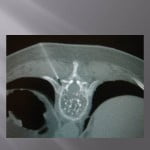

Biopsie sous guidage scanner